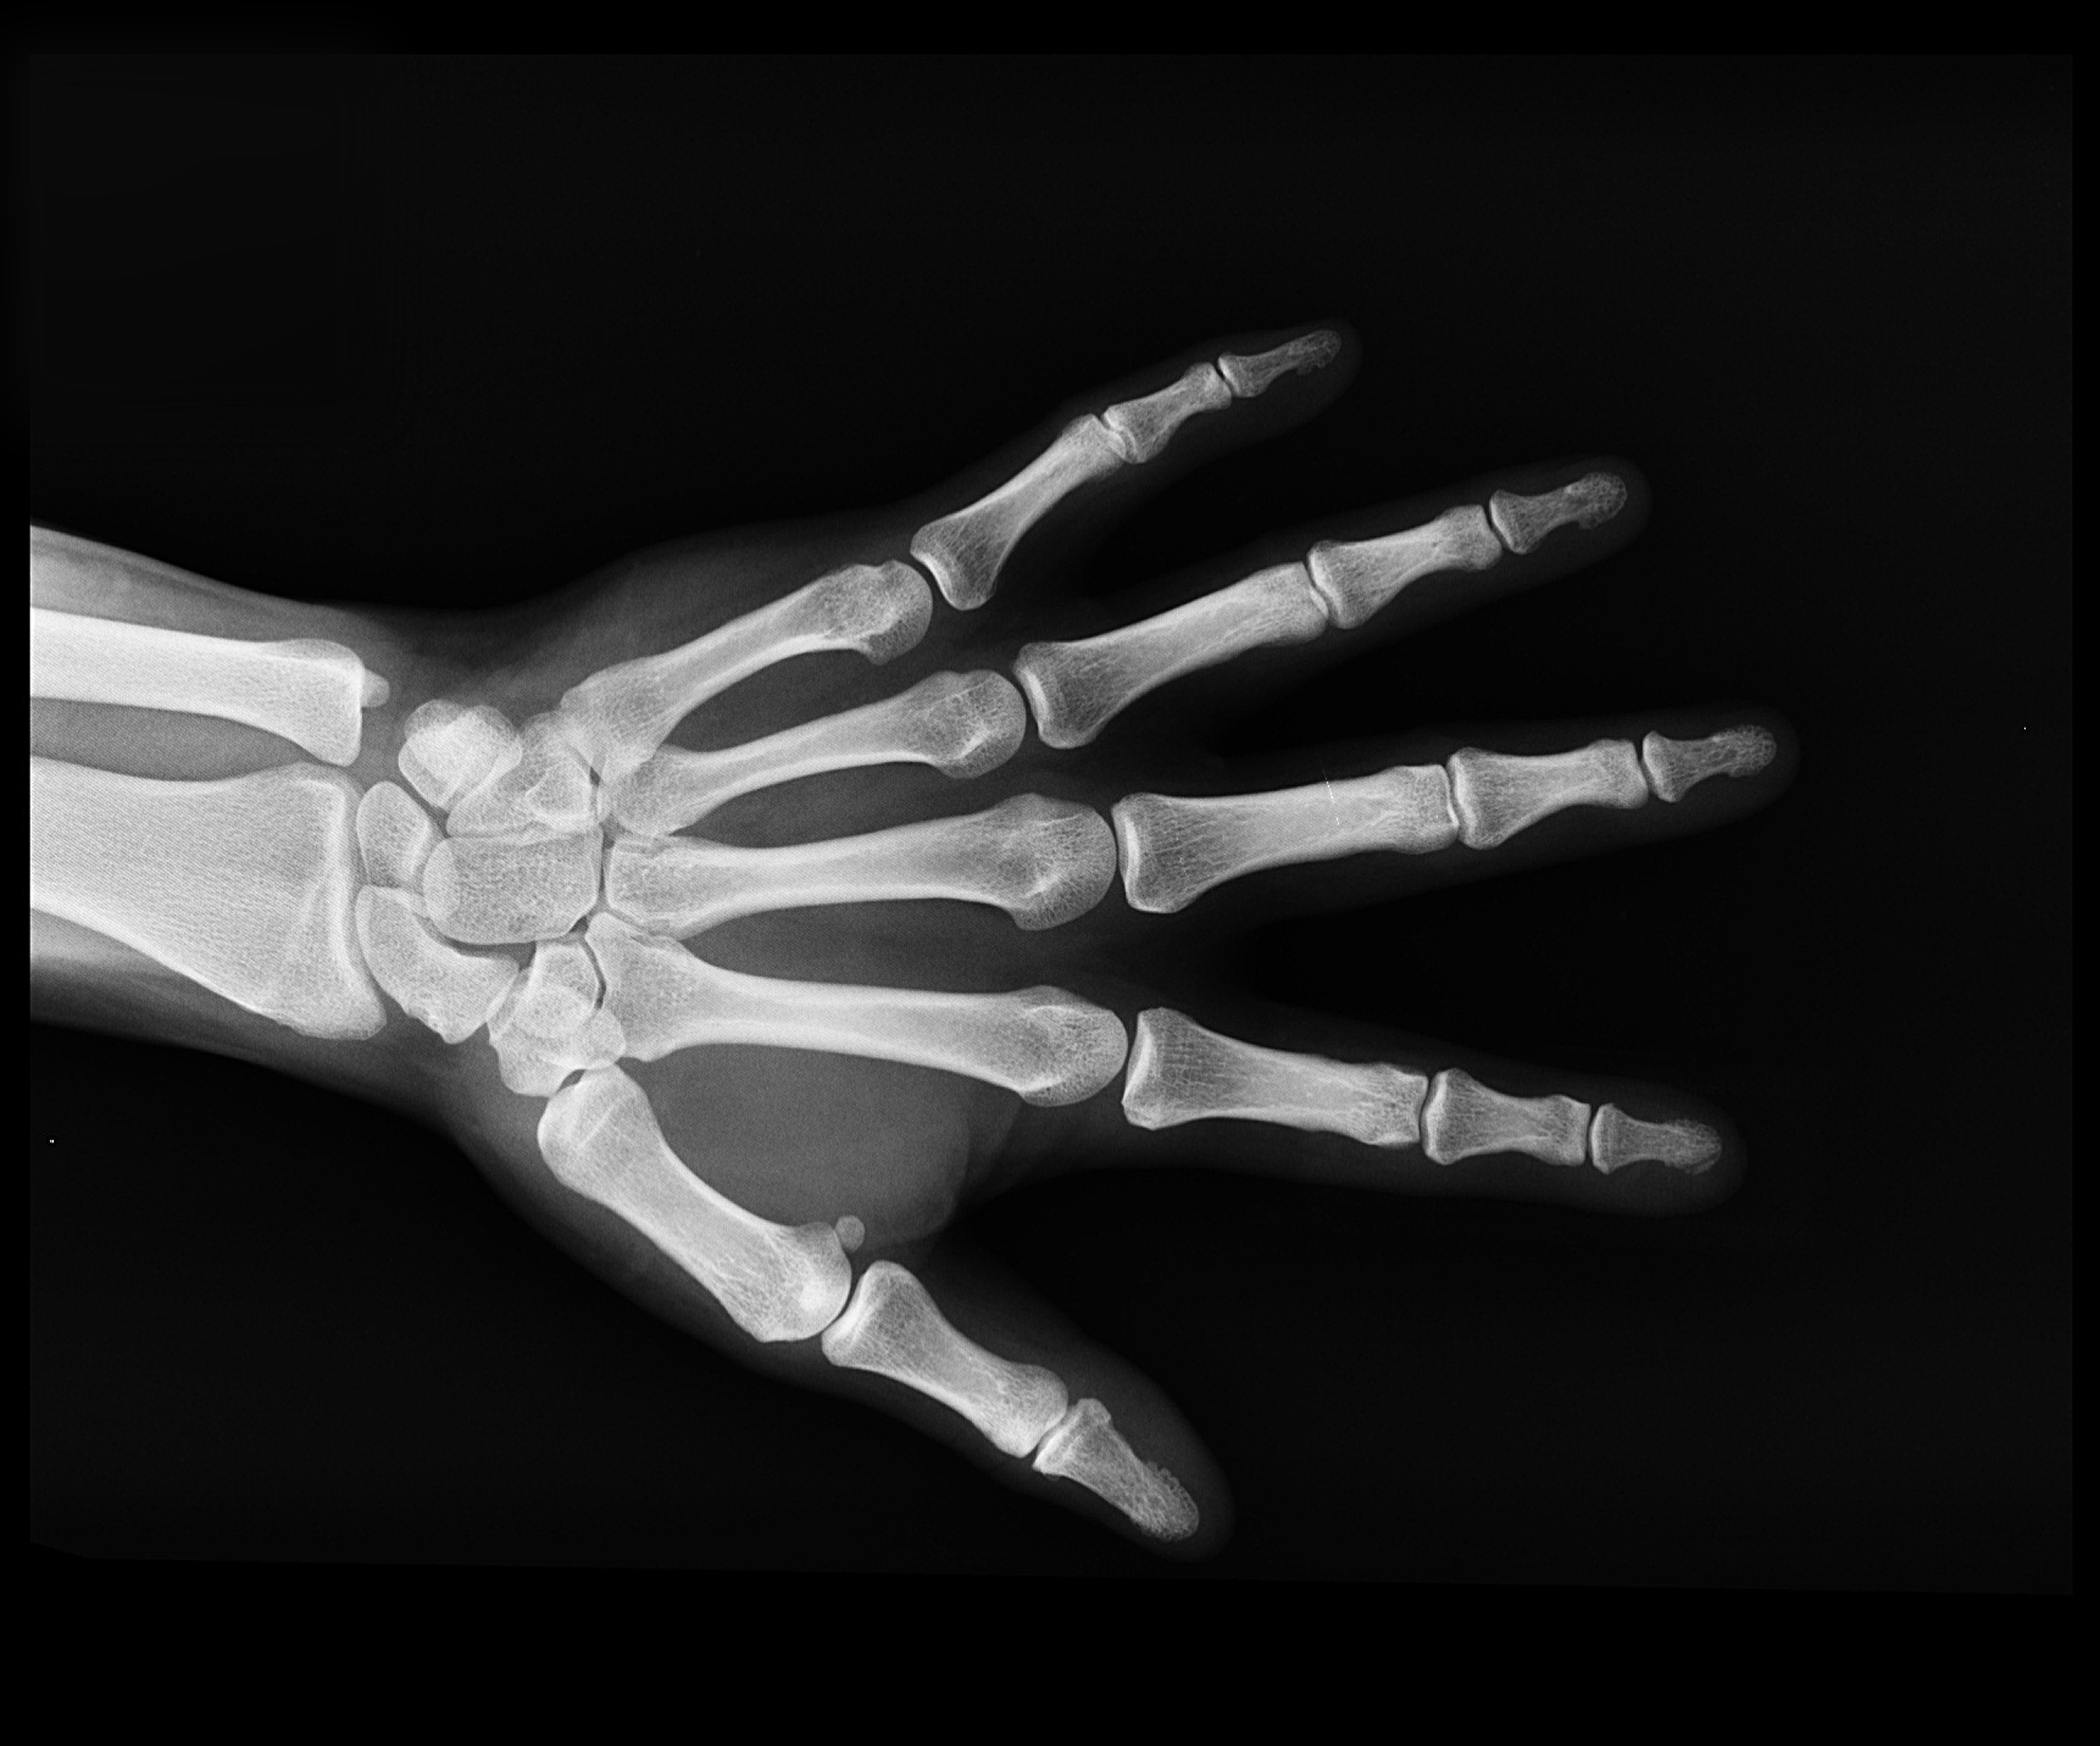

Um fratura nos minúsculos sesamóides, dois ossinhos tão ridículos quanto necessários do dedão, me proporcionou uma série de experiências baseadas em observações e agitou a semana que prometia ser de pasmaceira no noticiário e entediada no cotidiano. A começar pela prova de quanto o corpo humano pode ser frágil e o ser humano, dependente.

Com a necessária imobilização do local fraturado, perde-se o movimento de uma das mãos e se restringe uma série de atividades para as quais damos pouca importância mas que podem se transformar em desafios que exigem malabarismo e súplicas de solidariedade. Tente amarrar o cadarço do sapato com uma só mão ou abotoar o punho da manga da camisa sem a mão do lado oposto – sim, eu sei, a humanidade tem coisas mais importantes com que se preocupar.